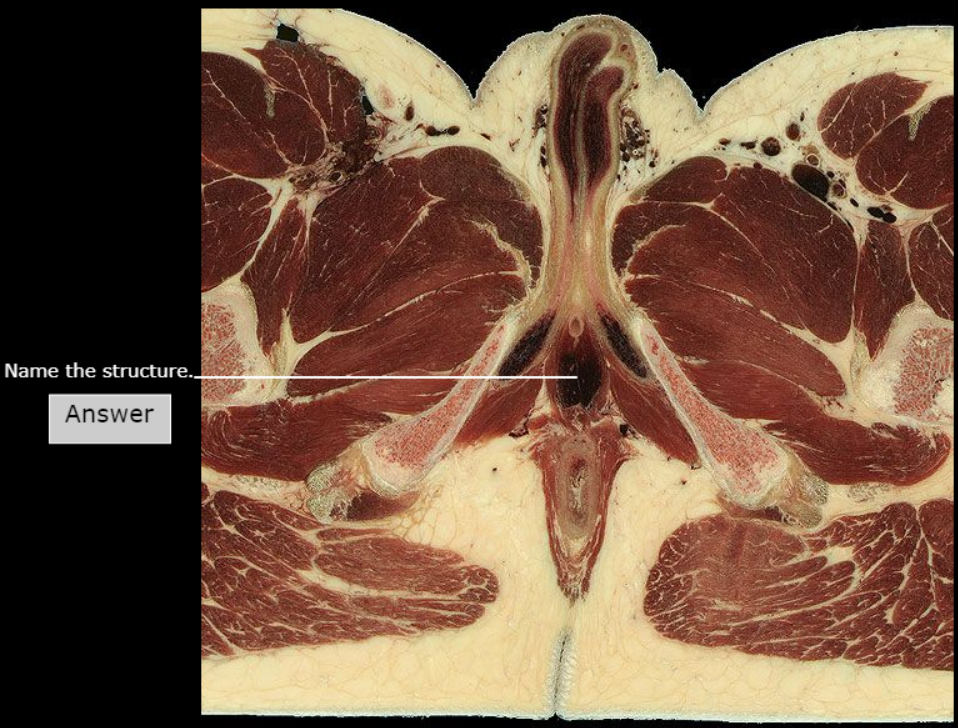

Tendinous Arch of Levator ani